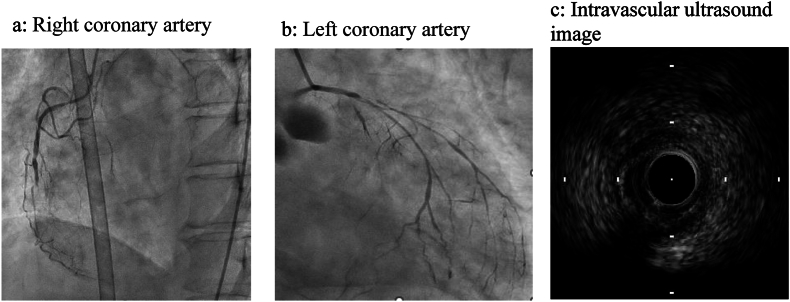

Abstract Image